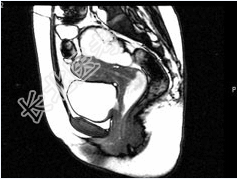

- 多项选择题女,28岁, 阴道有异常液体流下,CT和MRI扫描如图, 以下诊断正确的是( )

A、MRI的T2加权像示宫颈阴道内有大片状高信号影

B、CT增强示造影剂由膀胱进入阴道

C、膀胱后下缘可见鸟嘴状突起

D、考虑为膀胱阴道瘘

E、考虑为左侧输尿管异位开口